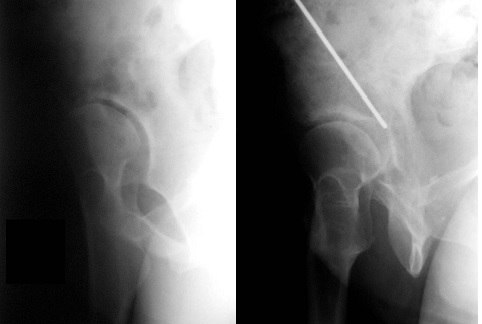

Chory w wieku 17 lat trafił do Izby Przyjęć z powodu urazu wysokoenergetycznego doznając silnego stłuczenia okolicy biodra prawego. Po badaniu klinicznym lekarz zlecił badanie radiologiczne miednicy, na którym stwierdził złamanie typu Pipkina z przemieszczeniem ponad 2 mm. Zaproponuj ewentualne dalsze badania i postępowanie lecznicze: